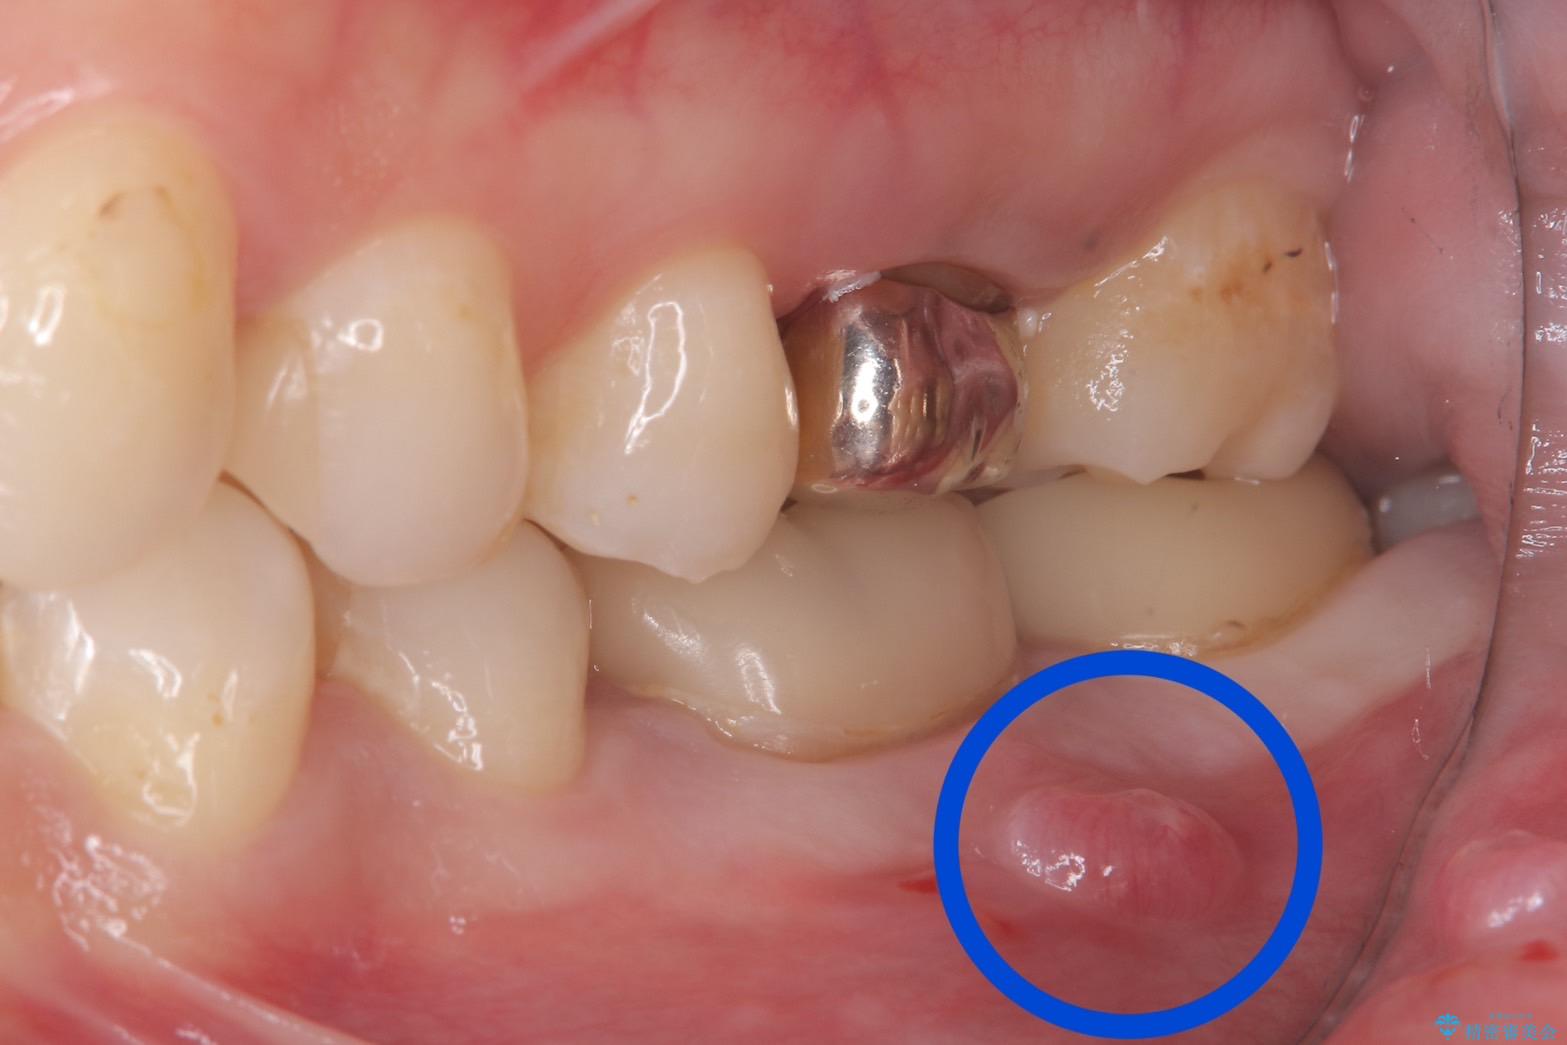

保存が難しい左下6番目の歯を抜歯し、左下8番目の歯(親知らず)を抜歯窩に移植しました。歯牙移植後の動揺防止のため暫間固定を行っています。

また移植後2週間経過時点で根管処置が必要となります。

骨との定着を確認し、今後矯正治療を行う予定のためレジン冠をセットしています。